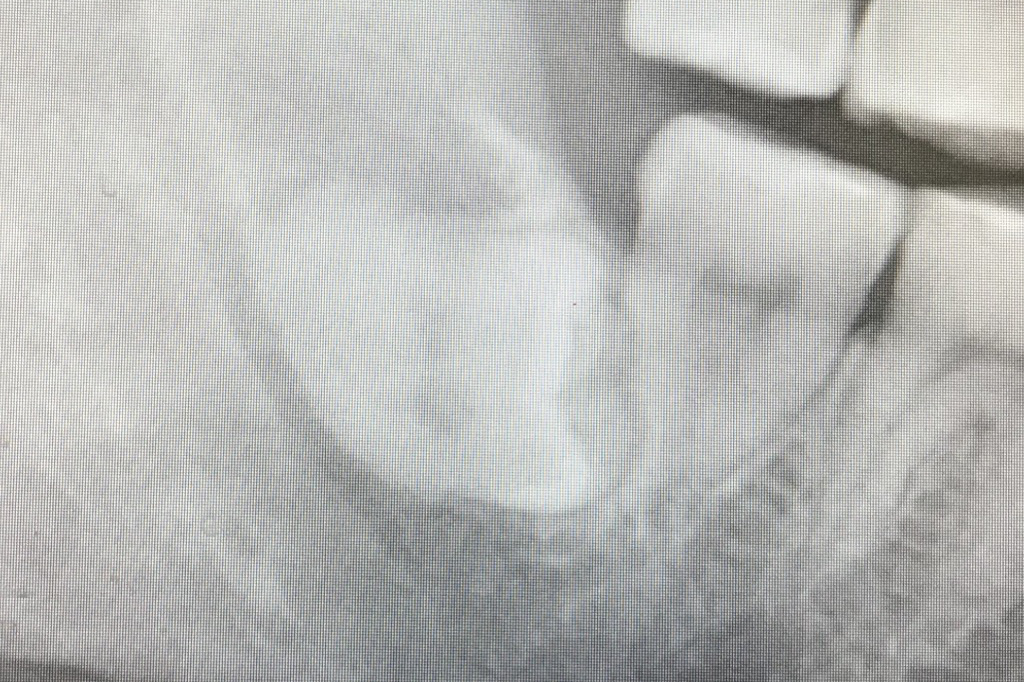

☆☆☆☆☆

おや,簡単そうな上の親知らずですね....と思うなかれ.実は虫歯が深くて,道具をかけるとボロボロと崩れてしまいます.

抜けた歯です.歯の頭が折れてしまい根っこだけ骨の中に残ってしまいました.歯茎をたくさん切って骨を削り飛ばして,ようやく抜けました.上顎洞も近いし,大変です.

抜歯した歯とレントゲンを重ねると,こんな感じになります.処置は30分もかかりました.虫歯が無ければ...1分もかかりません.みなさま,お願いです.抜歯は早めに決心してください.お互いハードモード突入してしまいます.